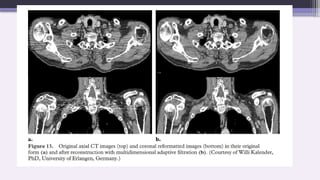

2. Adaptive Filtration

This software correction smooths the attenuation profile in areas

of high attenuation before the image is reconstructed.

A multi-dimensional adaptive filtration technique is used on

multi-section scanners.

For the small proportion of projection data that exceed a selected

attenuation threshold, smoothing is carried out between adjacent

in-plane detectors and between successive projection angles

while the z filter used in helical reconstruction is broadened for

high-attenuation projection angles to allow more photons to

contribute to the reconstruction